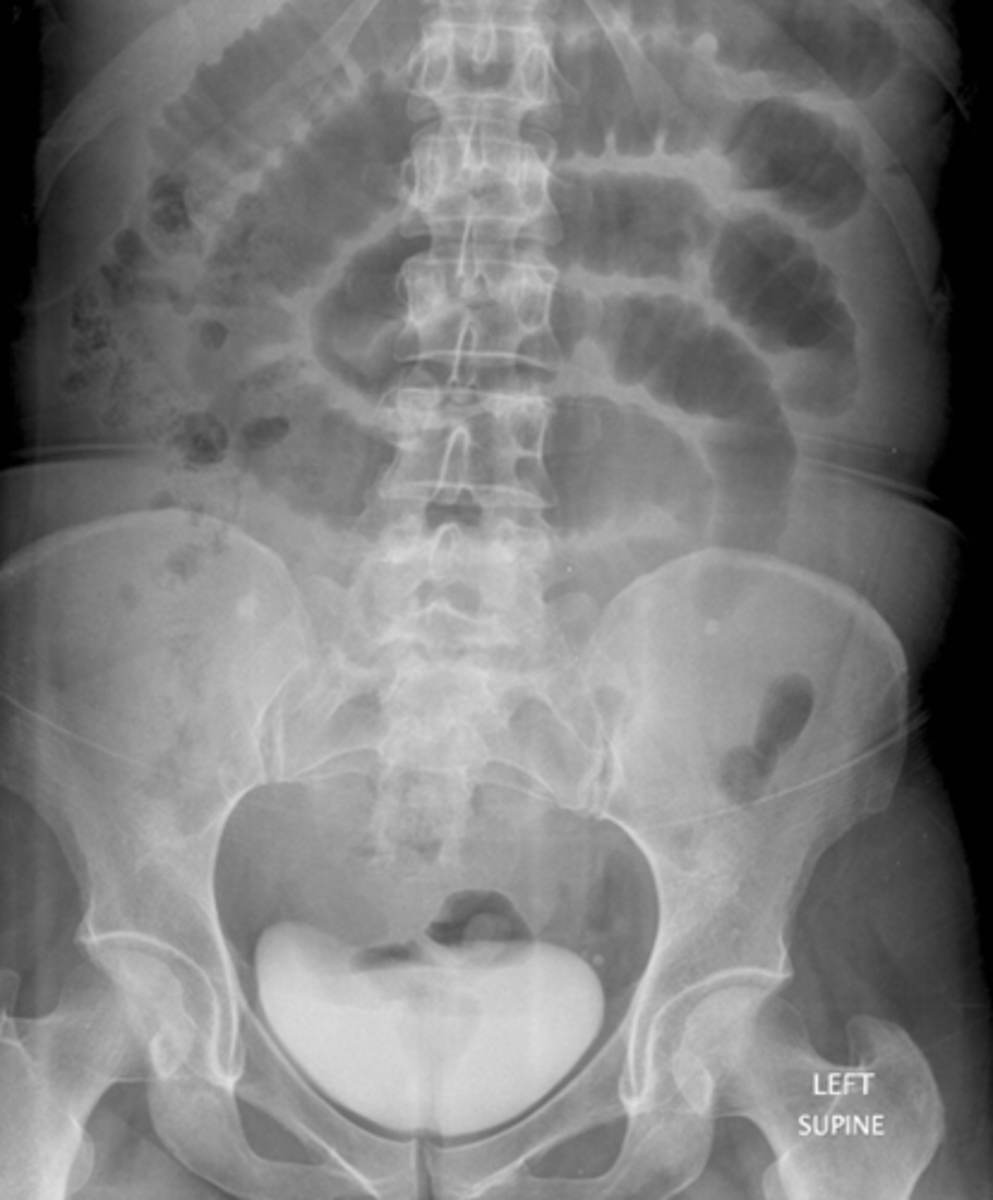

Normal prone abdomen

BLACK ARROW: S-shaped rectosigmoid colon.

WHITE ARROWS: air throughout the remainder of colon

In prone position, ascending, descending and rectosigmoid colon are the highest parts of the large bowl and will fill with air.